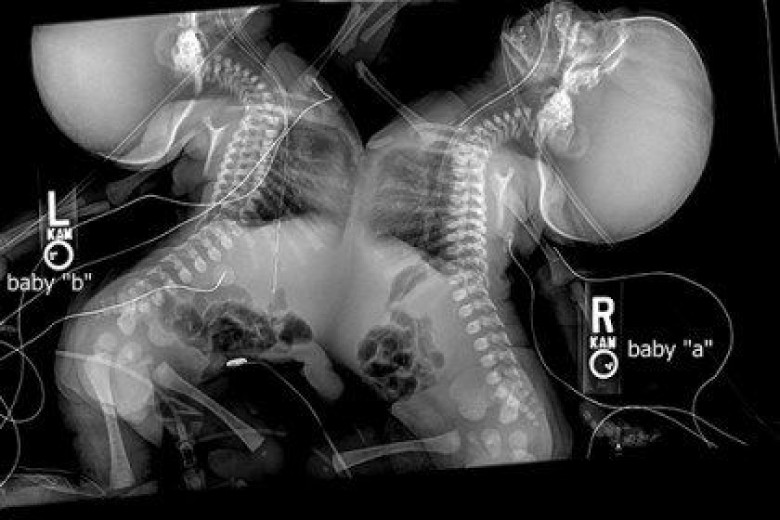

Տեսնելով ուլտրաձայնային հետազոտության արդյունքները՝ բժիշկները խորհուրդ տվեցին այս կնոջը ընդհատել հղիությունը. Մայրական սիրտը դեմ էր… (լուսանկար)

Շելլի և Գրեգ Տակերներն ամուսնացել են 2009 թվականին, և շուտով ծնվել է նրանց առաջնեկը՝ Օուենը: Բայց նրանք որոշեցին չսահմանափակվել, և Օուենին քույր կամ եղբայր նվիրել: Բայց դրա հետ կապված մեծ խնդիրներ առաջացան: Սկզբում Շելլին երկար ժամանակ չէր կարողանում հղիանալ:

Նա անպտղության դեմ բուժման կուրս անցավ և դա օգնեց նրան: Նրանք իմացան, որ շուտով իրենց ընտանիքում նոր փոքրիկ է հայտնվելու: Շելլին կրծքի տակ երկվորյակներ էր կրում: Բայց նրանք ժամանակից շուտ էին ուրախացել…

Ուլտրաձայնային հետազոտության արդյունքները ցույց տվեցին, որ երկվորյակները սիամական էին:

Բժիշկները զգուշացրեցին Տակերներին, որ երեխաներին բարեհաջող առանձնացնելու շանսերը շատ քիչ են: Այդ պատճառով էլ նրանք առաջարկեցին Շելլին ընդհատել հղիությունը: Բայց մայրիկն այդպես էլ չկարողացավ այդպիսի որոշում կայացնել:

Մայրիկը չհրաժարվեց իր երեխաներից, և կրեց նրանց 9 ամիս: Աղջիկները ժամանակին լույս աշխարհ եկան՝ կեսարյան հատման միջոցով:

Աղջիկներին անվանեցին Էլիսոն Ջուն և Ամելի Լի: Երեխաներին բաժանելու համար, պետք էր, որ նրանք մի փոքր մեծանային և ամրանային: Վիրահատությունը նշանակվեց, երբ նրանք ութ ամսական դարձան:

Մինչ դա, երեխաները մեծանում էին բժիշկների հսկողության տակ: Բարեբախտաբար, նրանց զարգացման ընթացքում, ոչ մի շեղում չէր եղել: Եվ աղջիկները լավ պատրաստված էին նշանակված վիրահատությանը:

40 բուժաշխատողներից բաղկացած խումբը 7 ժամ շարունակ աղջիկների բաժանման շատ բարդ վիրահատություն կատարեց: Չնայած բարդ վիրահտությանը՝ ամեն ինչ շատ լավ անցավ:

Էլիսոն Ջունը և Ամելի Լին վերջապես «ազատվեցին, բաժանվեցին» միմյանցից:

Տեսնելով իր աղջիկների առաջին քայլերը՝ մայրիկը շատ ուրախ է, որ ժամանակին ճիշտ որոշում է կայացրել: